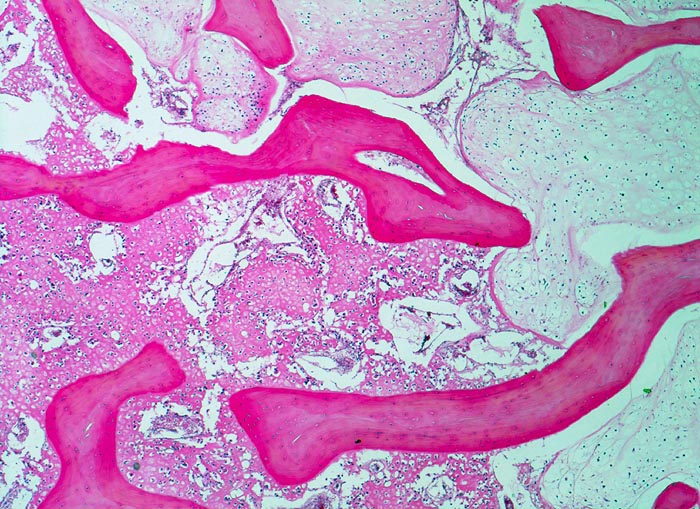

In der Übersicht ist die scharfe Grenze zwischen hochdifferenziertem Chondrosarkom (rechts) und dedifferenzierter Osteosarkomkomponente (links) sichtbar.

An anderer Stelle gleicht der Tumor einem malignen fibrösen Histiozytom.

Dedifferenzierte Chondrosarkome sind dadurch gekennzeichnet, dass Anteile eines hochdifferenzierten Chondrosarkoms abrupt übergehen in Anteile eines hochmalignen Tumors (Osteosarkom, Malignes fibröses Histiozytom...). Im Gegensatz zum Osteosarkom bestehen beim dedifferenzierten Chondrosarkom keine fliessenden Übergänge zwischen den unterschiedlichen Komponenten und die Chondrosarkomkomponente ist höher differenziert als im Osteosarkom mit chondroider Matrixbildung.